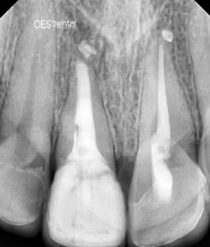

Realizamos radiografía panorámica y periapical de la zona, donde podemos observar que le queda un resto radicular, el cual presenta una gran infección periapical, parece llevar intraconducto un material intraconducto y una obturación provisional sobre el mismo. Esta obturación provisional está completamente suelta y filtrada.

- Apicoformación con MTA del resto radicular que presenta para la formación de un stop apical y su posterior tratamiento endodóntico con técnica de obturación termoplástica.

Procedemos a la realización del tratamiento conservador. Empezando por la apicoformación, endodoncia y restauración del diente. A continuación podemos ver una sucesión de radiografías con la evolución del tratamiento del paciente y la intervención realizada.